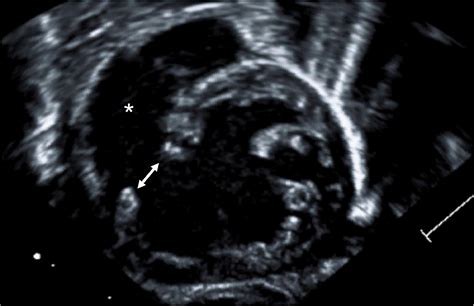

Modern advancements in pediatric cardiology have made early detection of Double Inlet Left Ventricle much more accurate. In many cases, the condition is identified during a prenatal fetal echocardiogram, allowing for a planned delivery at a specialized cardiac center. After birth, infants are monitored closely through a variety of diagnostic tools.

Fetal Echocardiogram Early visualization of heart chambers during pregnancy.